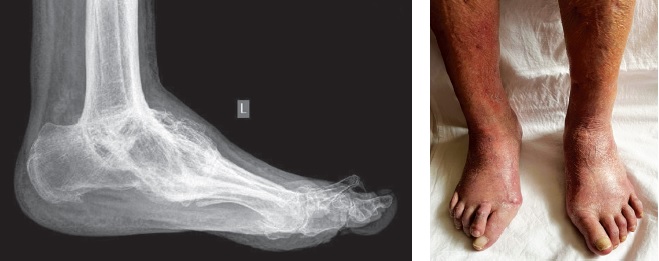

We present the use of this technique in a clinical case of a 72-year-old female patient with distal neuropathy without diabetes. A year before seeking treatment, she noticed progressive left foot deformity, was observed on an outpatient basis. Conservative treatment and orthotic use for one year yielded no improvement (Figure 2).

Figure 2. Photograph and X-ray of the foot and ankle joint before inpatient treatment